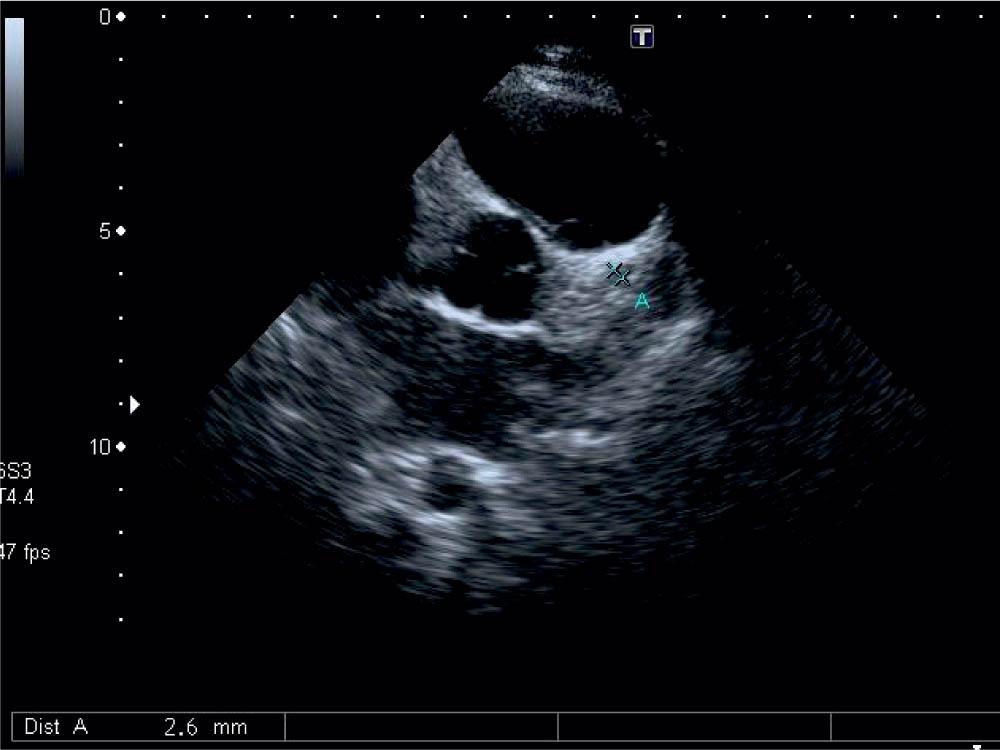

Figure 1